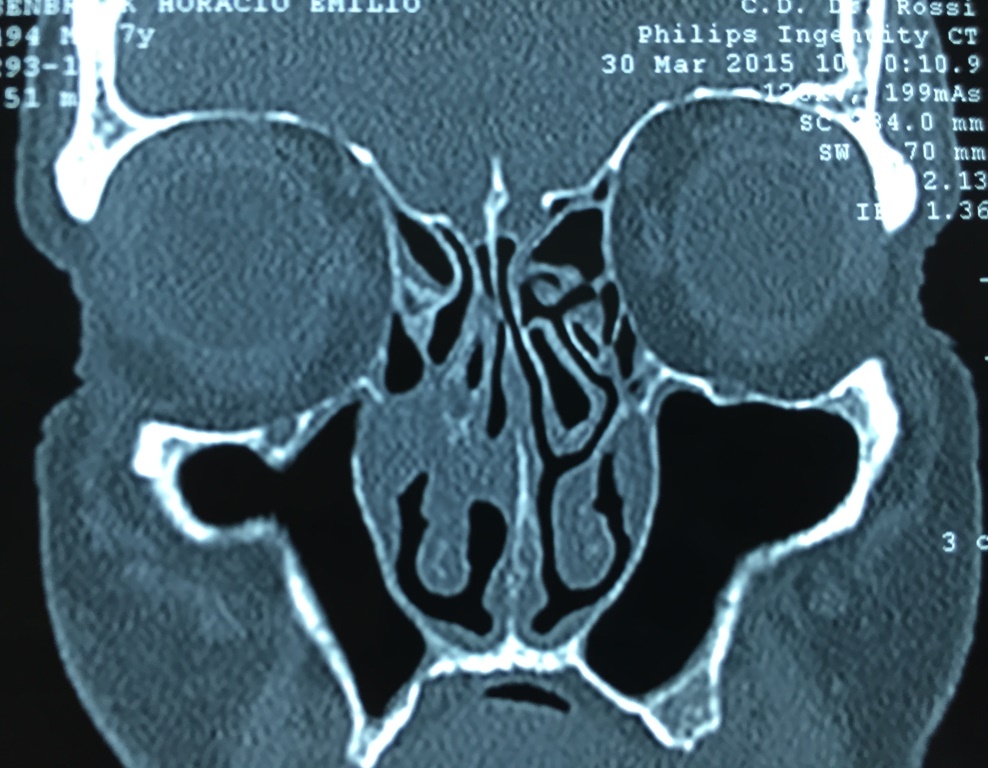

Se realizó tomografía computarizada, en la que se observa imagen irregular de aparente lesión, no circunscrita, que compromete el drenaje del meato medio e inferior con superposición en la parte posterior del cornete medio, sin presencia de lesiones de características similares contralaterales (Figura 1).